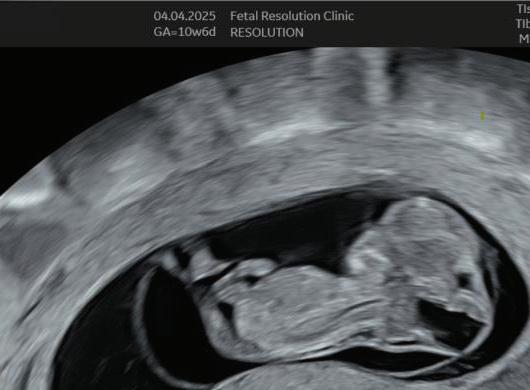

The first trimester— spanning from conception to 13+6 weeks—is no longer considered a “blind phase” of pregnancy. With the evolution of highresolution ultrasound, color Doppler and advanced biochemical screening, this period has transformed into a window of opportunity for early fetal evaluation, risk prediction and preventive strategies.

First-trimester fetal evaluation is not limited to dating the pregnancy or confirming viability—it is the foundation of predictive, preventive, and personalized obstetric care.

1. EARLY PREGNANCY SCAN (6–10 WEEKS)

Indications:

1. Confirmation of pregnancy.

2. location of pregnancy.

3. Number of fetus.

4. Cardiac activity.

5. Initial dating.

6. Assessment of uterine contour to ruleout any uterine anamolies.

7. Examnation of adenexa.

Findings:

• Gestational sac at ~4.5–5 weeks-Appears as anechoic fluid filled structure surrounded by a decidual reaction (Double Decidual sac sign).

• Measure Mean sac diameter .

• Yolk sac appear around ~5–5.5 weeks.

• Embryo with cardiac activity around 6 weeks.